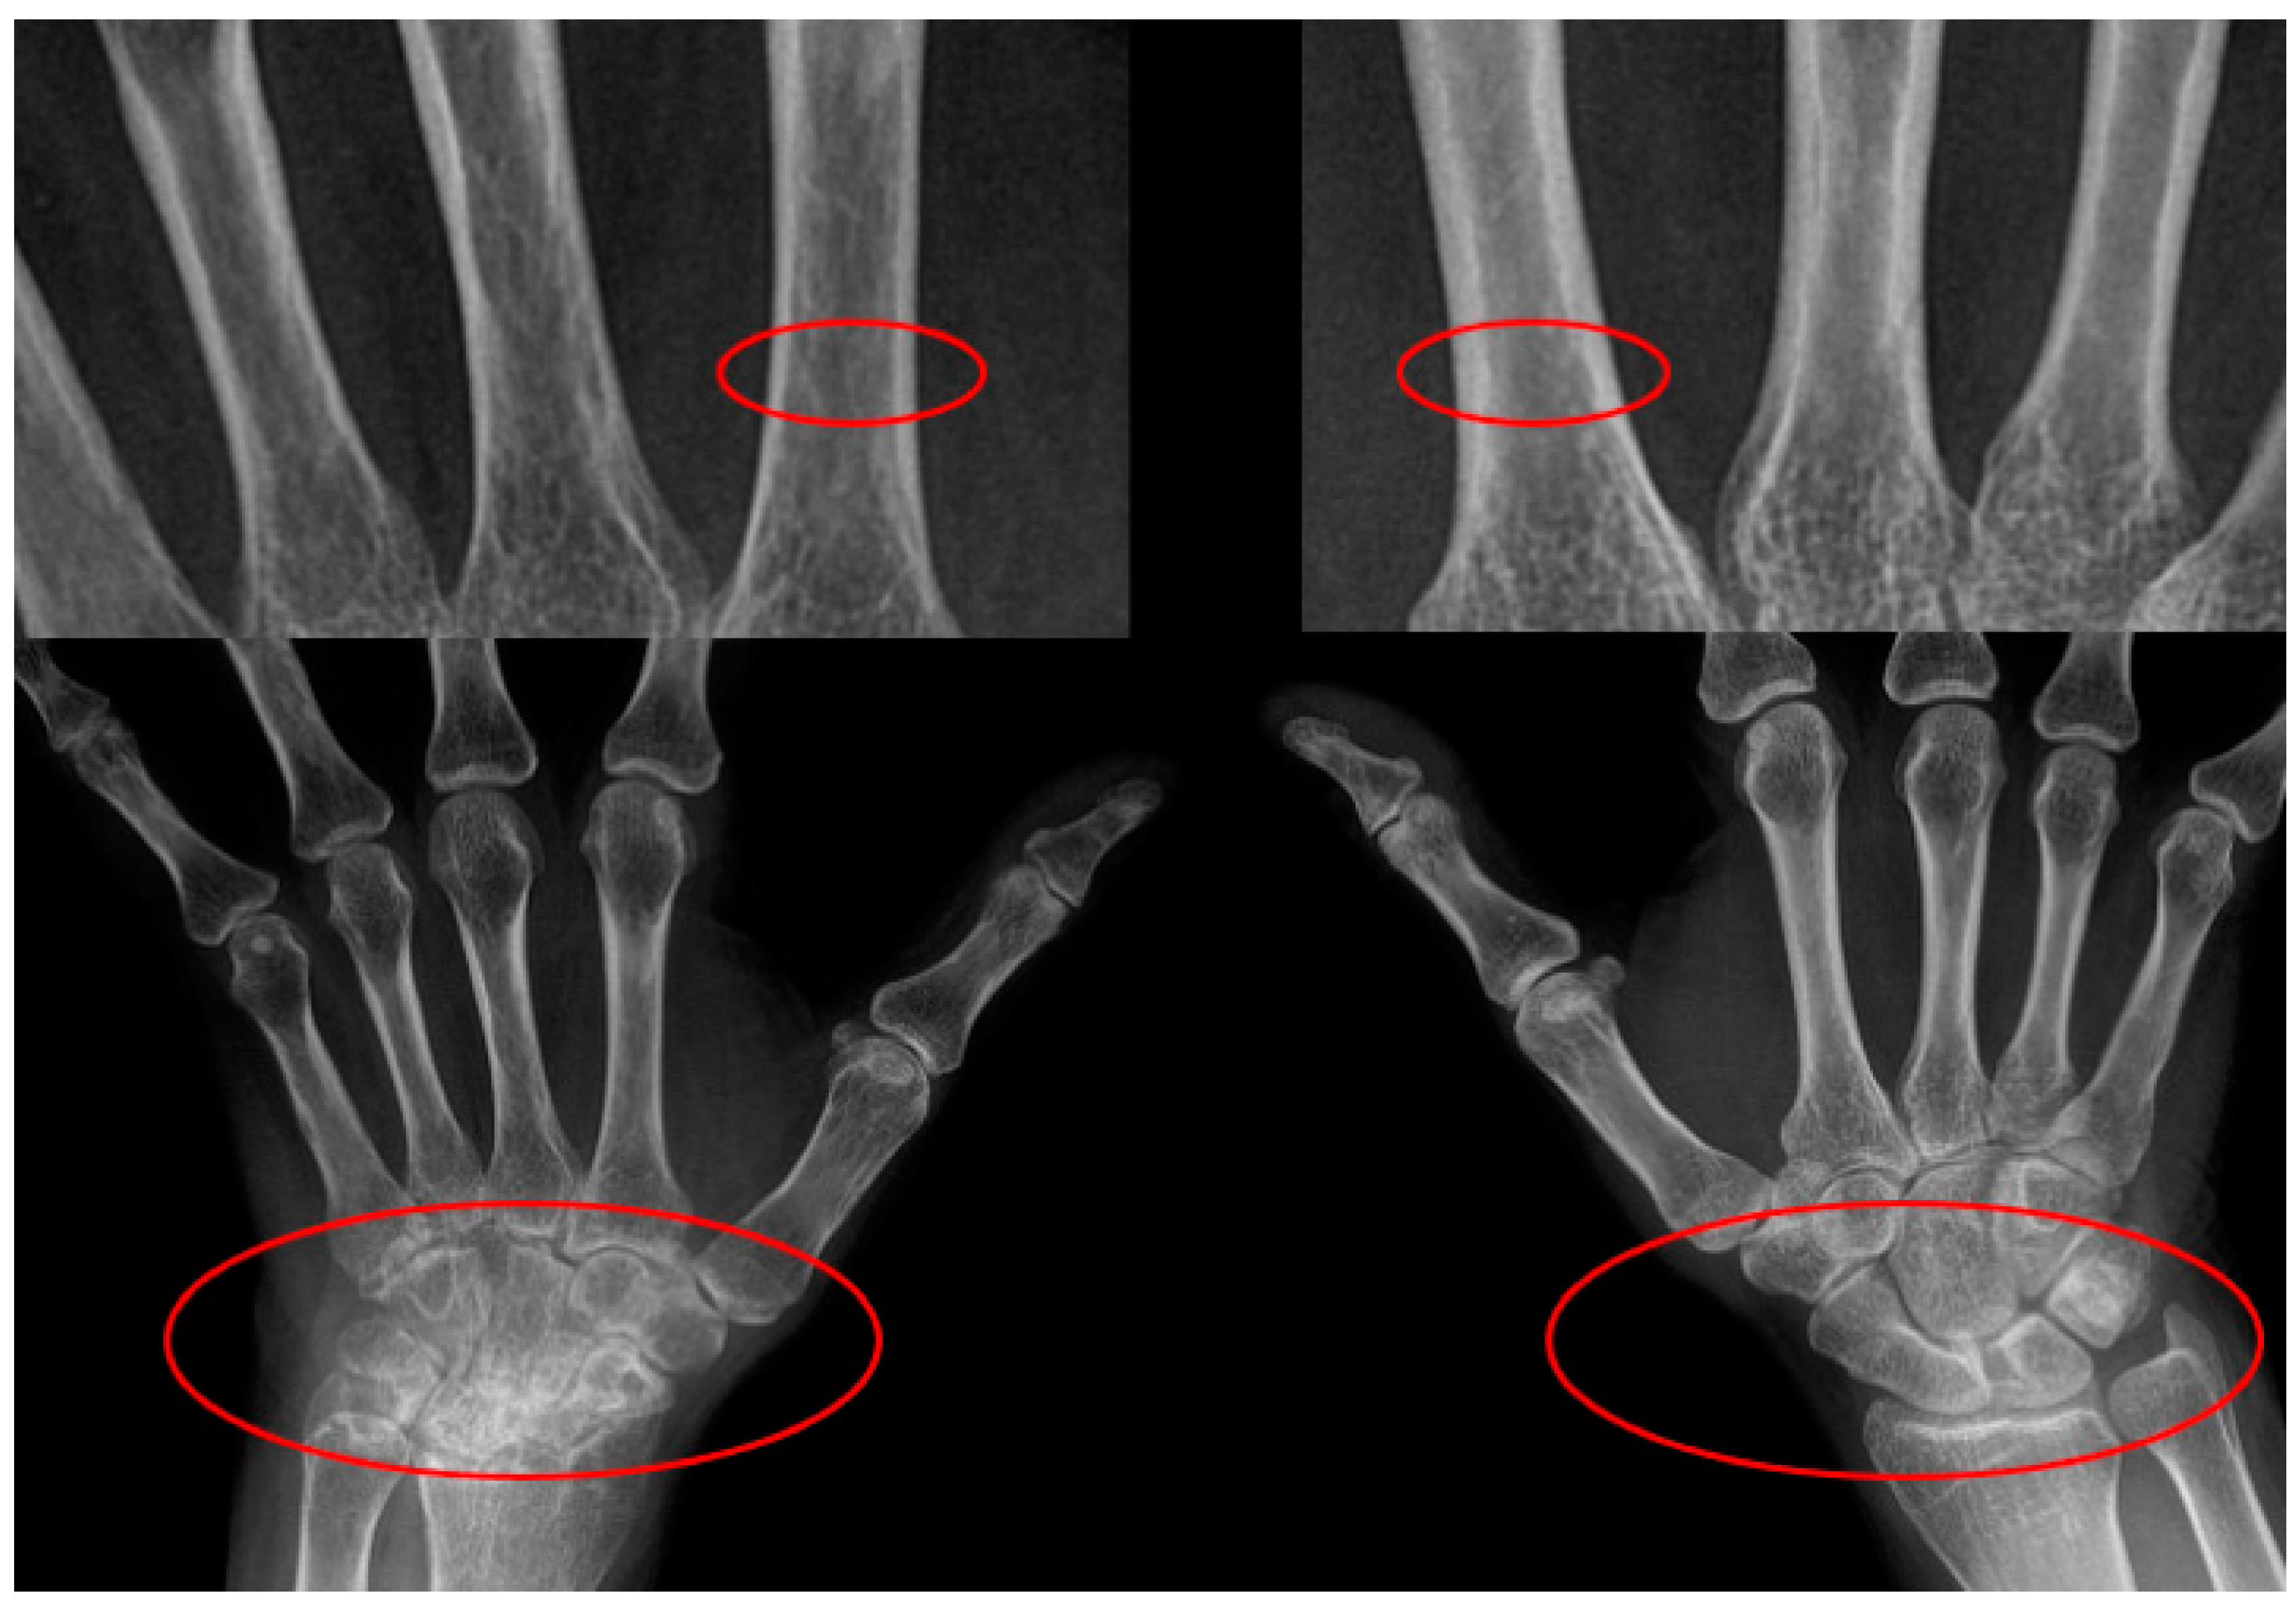

Asymmetrical Damage of the Wrist Joint Induces Lateralized Cortical Bone Loss in the Metacarpal Diaphysis in Patients with Rheumatoid Arthritis

3.2. Metacarpal CTR

3.3. Damage to Wrist and Metacarpophalangeal Joints

3.4. Unilateral Reduction of Metacarpal CTR

3.5. Comparative Analysis of Laterality in Metacarpal CTR and WJD